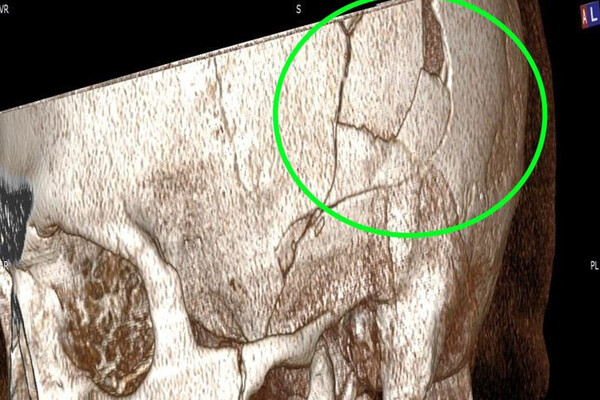

Хирурги Новосибирской ГКБ № 34 спасли мужчину, на голову которого упала коробка передач от«КамАЗа» весом 200 кг. Об этом сообщает Минздрав области.

Пациента доставили в больницу с рабочего места, где он занимался ремонтом «КамАЗа», когда ему на голову упала коробка передач весом 200 кг. Он получил тяжелую травму с повреждением костей и смещением костных фрагментов в полость черепа.

Требовалось срочное хирургическое вмешательство, врачам пришлось заново собирать черепную коробку. Нейрохирургам удалось восстановить целостность черепа без применения имплантов и внешних вставок.